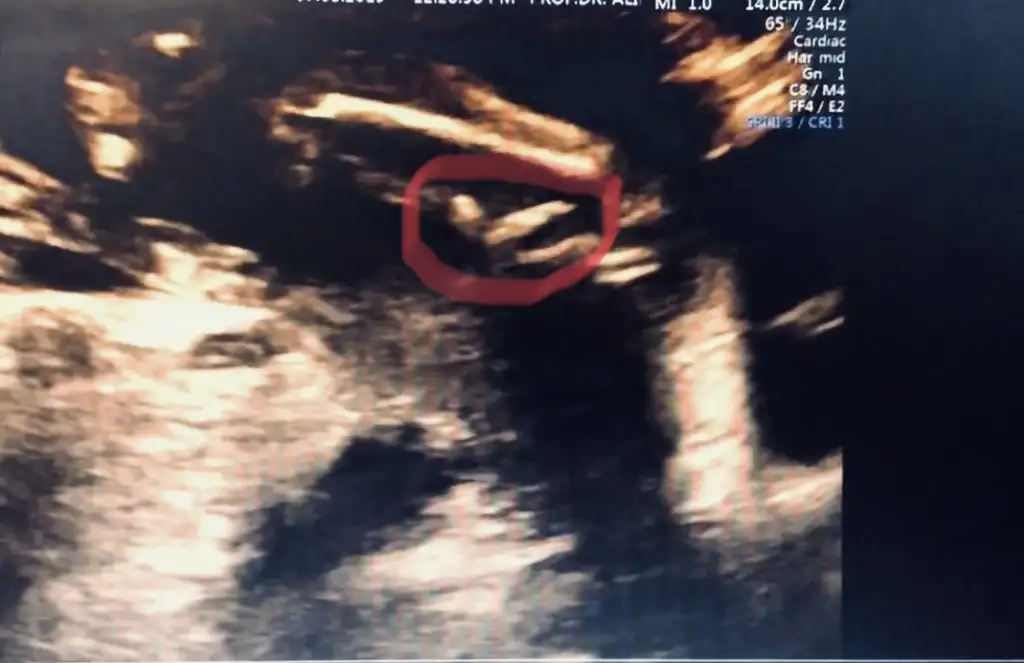

Erkek diyorum daha net usg varmı![]()

İnsallah kizdir. Kiz istiyoruz da nasip kismet. Saglikla hayirla gelsin de cok farketmezKız diyorum

Erkek gönlünüzdeki saglıkla nasip etsin rabbim

Ay inşallah kızdır Canım ikra erkek demiş o bende çok daha iyi biliyoİnsallah kizdir. Kiz istiyoruz da nasip kismet. Saglikla hayirla gelsin de cok farketmez